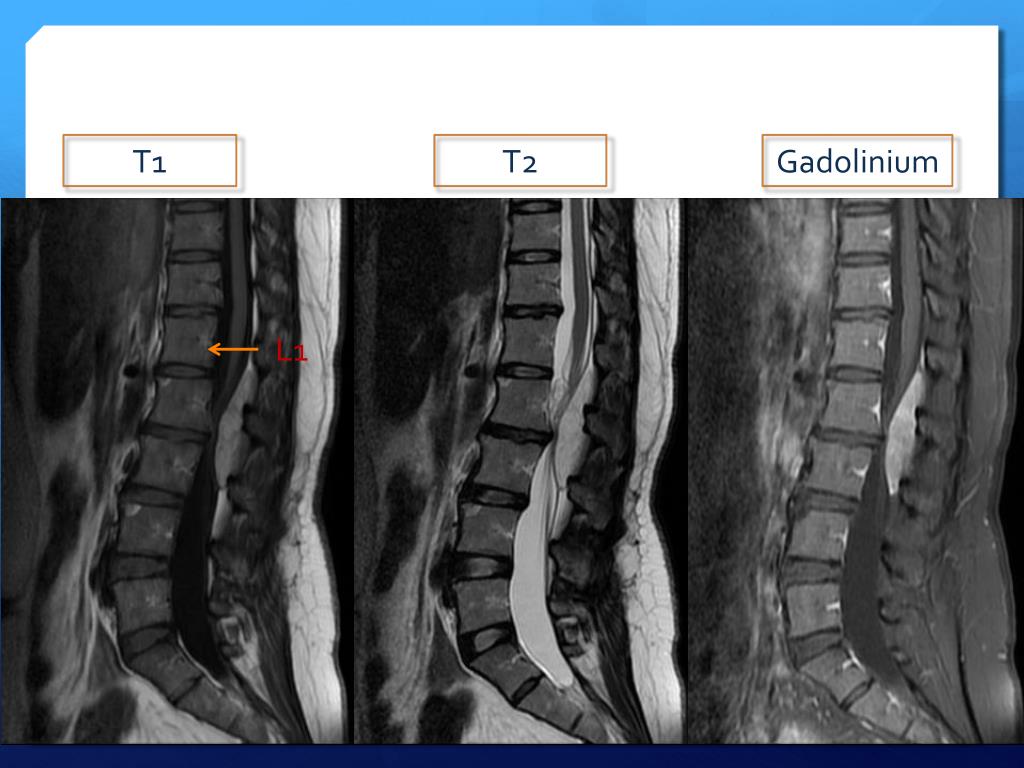

7. Image T2 T1 Gadolinium T9 L1

8. Problem List & plan T9-11 epidural spinal tumor Arrange laminectomy and tumor excision

16. T2 T1 Gadolinium L1